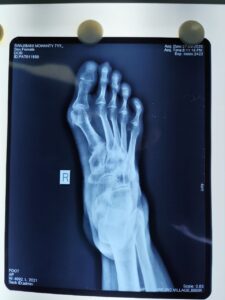

Minimally invasive foot surgery is an advanced surgical technique performed through very small incisions using specialized instruments and imaging guidance. Unlike conventional surgery, MIS reduces trauma to surrounding muscles and tissues, resulting in less pain, minimal scarring, and faster healing.

Bunions (Hallux Valgus)

Foot Arthritis

Accurate diagnosis using modern imaging